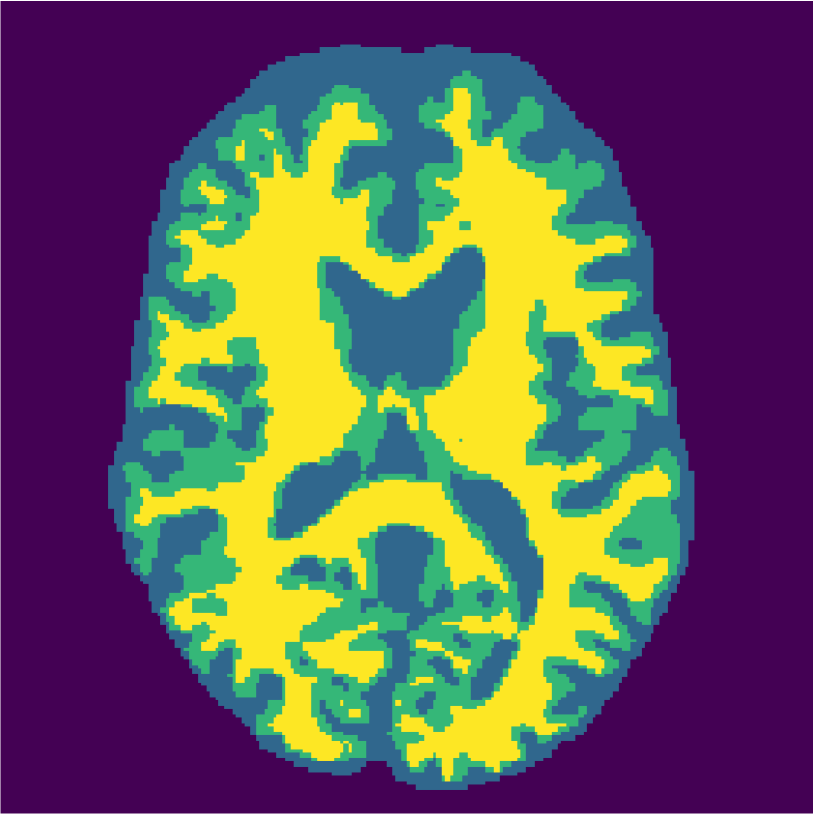

Appendix A describes the nuclear magnetic resonance (NMR) relaxation times for the tissues in the Brainweb anatomical models, for 1.5 and 3.0 Tesla field strengths. The tissues in the anatomical models are grouped into ”background” (BKG), ”cerebrospinal fluid” (CSF), ”gray matter” (GM), and ”white matter” (WM) to compose the ground truth segmentation labels for the simulated scans. The simulations result in images of 256 by 256 pixels, with a 1.0x1.0mm resolution. Figures 5(a) and 5(b) show examples of the Brainweb1.5T and Brainweb3.0T scan of the same subject. For all scans, we used a brain mask to strip the skull.

Figure 6 displays the manually selected patches and their position within the image. For both the source and target classifier, one target patch per tissue is insufficient to achieve good tissue classification performance (2 (top row): 0.631 and 0.613). However, the mrai-net classifier shows considerably better performance (0.223), using only one target patch per tissue. The proxy -distance also drops from near perfect separability (1.88) to near invariance (0.26). Randomly selecting (10 repeats) 1 target patch per tissue (Table 2 (bottom row)), shows worse performance of the mrai-net classifier, for both the classification error (0.250) as well as the -distance (0.41). Suggesting that purposive (information rich) sampling beats random sampling in this case.

Examples of the segmentation results on one of the target test images are shown in Figure 8 for experiment 2.1, Figure 9 for experiment 2.2, and Figure 10 for experiment 2.3. Examples are shown after using 1 target patch per tissue for training, and after using 100 target patches per tissue for training. The results show that only the mrai-net classifier is able to predict a segmentation that approaches the ground truth with only 1 target patch per tissue for training (error for experiment 2.1 = 0.269, experiment 2.2 = 0.403, experiment 2.3 = 0.320), while the source and target classifiers cannot (source error for experiment 2.1 = 0.667, experiment 2.2 = 0.653, experiment 2.3 = 0.435; target error for experiment 2.1: 0.591, experiment 2.2: 0.614, experiment 2.3 = 0.596). After using 100 patches the source and target classifiers can predict a gross segmentation of WM, GM and CSF (source error for experiment 2.1 = 0.213, experiment 2.2 = 0.384, experiment 2.3 = 0.363; target error for experiment 2.1: 0.205, experiment 2.2: 0.368, experiment 2.3 = 0.368), but the mrai-net classifier prediction shows more details and a lower tissue classification error (error for experiment 2.1 = 0.111, experiment 2.2 = 0.276, experiment 2.3 = 0.284).